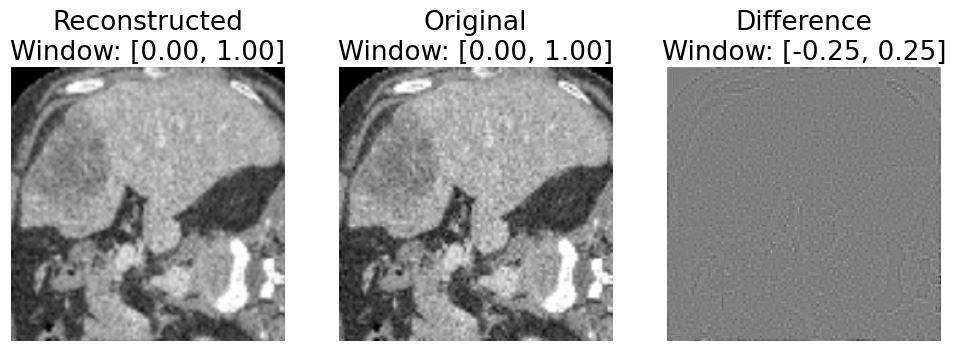

Refer to caption

Figure 2. Reconstruction error example (leftmost image is RR, middle image is OO). The rightmost figure is the difference ROR-O; there is visible non-uniform noise roughly following anatomical structures which is visible between the original image OO and the result after forward projection and backprojection RR. In all figures of CT images, the window is expressed in the format [a,b][a,b] where pixel intensities below aa are depicted in black, and pixel intensities above bb are depicted in white.

We observe a notable “reconstruction error” introduced by our simulation approach. In particular, when considering discrete images, the result of performing forward projection followed by backprojection is not equivalent to the original image, as seen in Fig. 2. We were not able to mitigate this error by increasing the number of projection samples to increase the sampling resolution for the transform. We believe this may be a consequence of using relatively small images with far fewer samples than can be obtained with a real CT scanner and a physical volume. Unfortunately, with our approach, this unintended reconstruction error becomes mixed with the intentional simulated distortions we apply in sinogram space (Fig. 3), muddying the conclusions which can be drawn regarding domain adaptation.